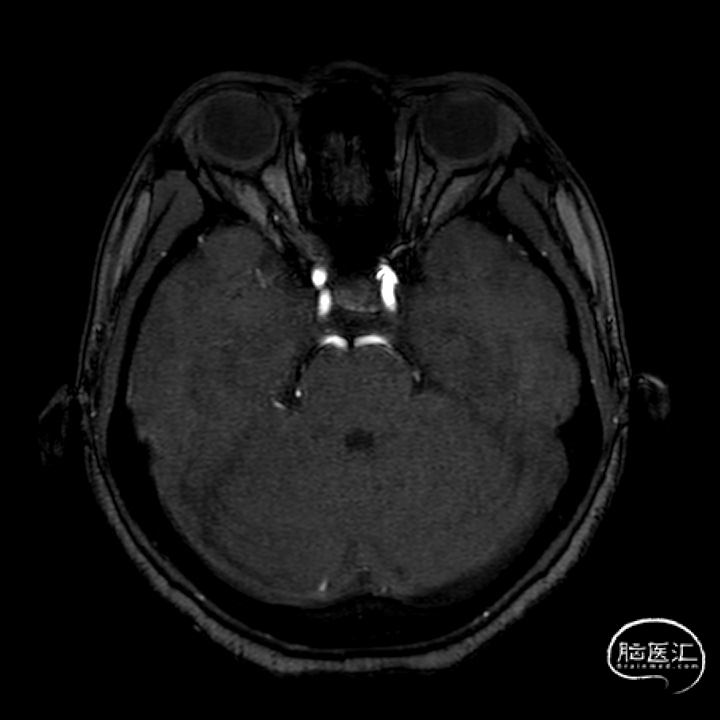

(A)

(B)

(C)

A:支架到位前造影确定动脉瘤位置以及拟释放支架位置;B:支架到位;C:支架到位后再次确定支架与动脉瘤位置关系。